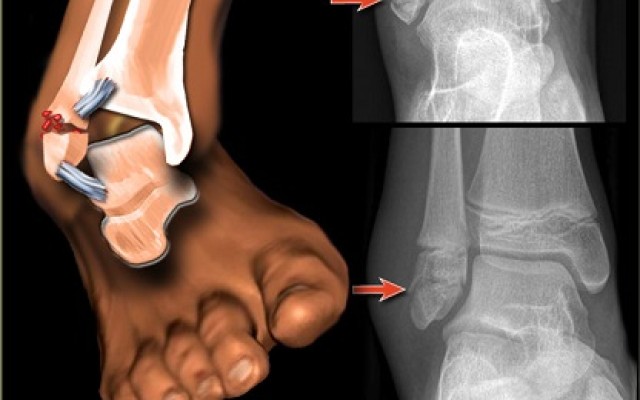

Chronic ankle instability is a condition characterized by a recurring giving way of the outer (lateral) side of the ankle. This condition often develops after repeated ankle sprains. Usually, the giving way occurs while walking or running on uneven surfaces or sloped surfaces. Most people who suffer an ankle sprain will recover with Physio and retraining. A select small number go on to develop...5 Steps to Finding the Perfect Life after Knee Replacement

Ankle fractures can occur during sporting activities, or as a result of a fall. Fractures can occur in the tibia, fibula or a combination of both, and damage can also involve the ligaments of the ankle joint. Depending on the type and location of the fracture, surgery may be required. Dr Kaushik Hazratwala - Ankle surgery specialist Depending on the success and stability of the...Orthopaedic Research Institute of Queensland (ORIQL)